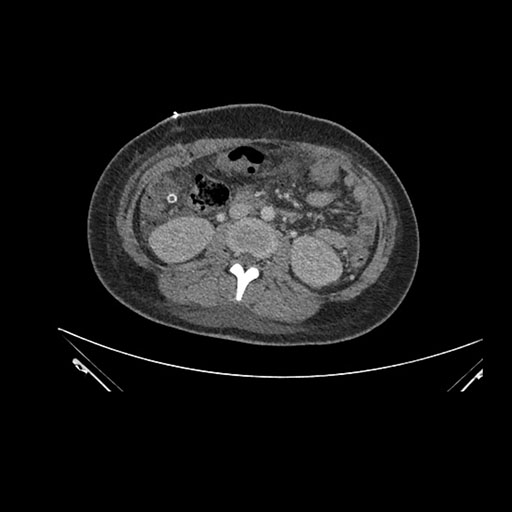

Axial Venous

Imaging analysis

Based on initial findings, which issue(s) would you be most concerned about?